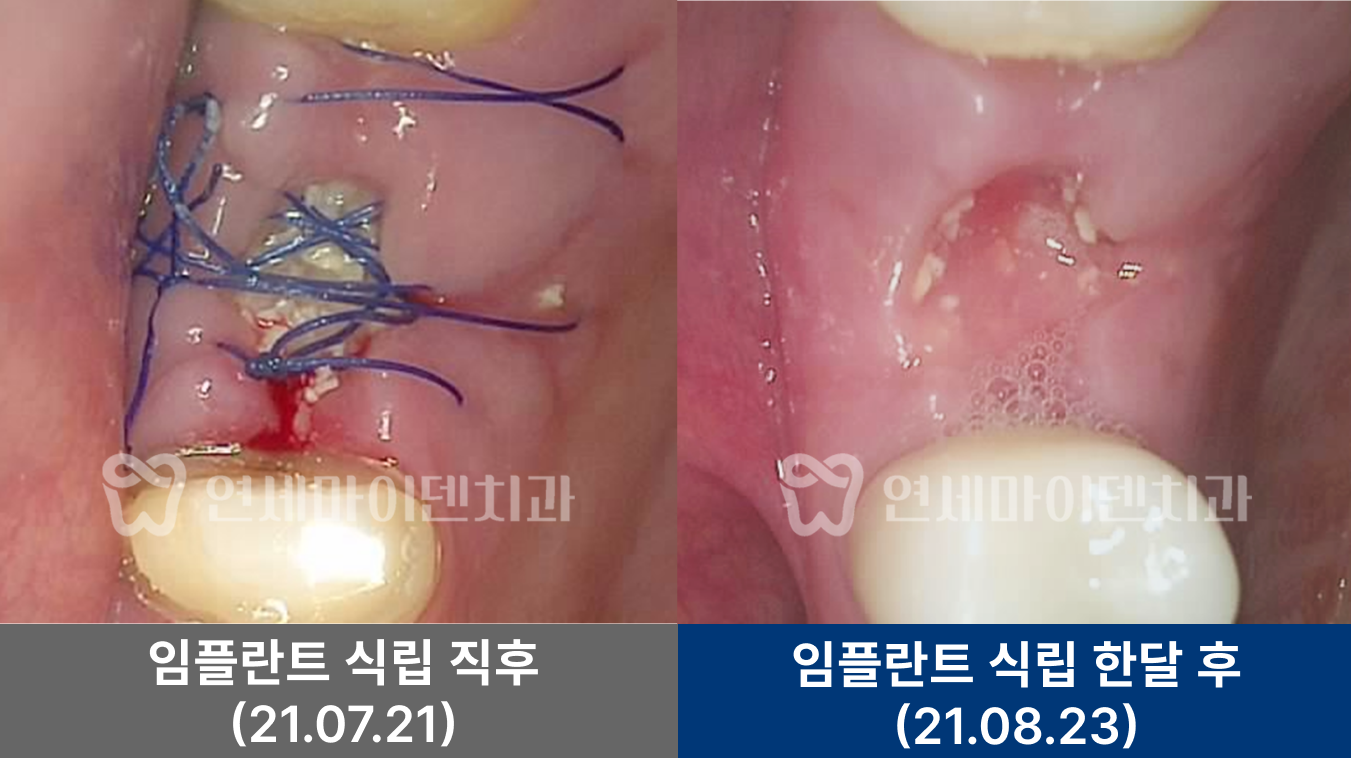

■ #25번 #26번 치아 수술 경과

임플란트를 시행한 부위 잇몸이 잘 치유되었고, 3년 후까지의 경과 관찰에서 임플란트 부위가 안정적으로 유지되고 있었습니다. 환자분도 음식물 끼임 없이 편하게 사용 중이십니다.

앞쪽 치아의 뿌리끝 염증도 소실되었습니다. 염증이 사라졌다는 것은 뼈 재생이 이루어졌다는 의미로, 이 치아의 통증도 완전히 해소되어 잘 사용하고 계십니다.